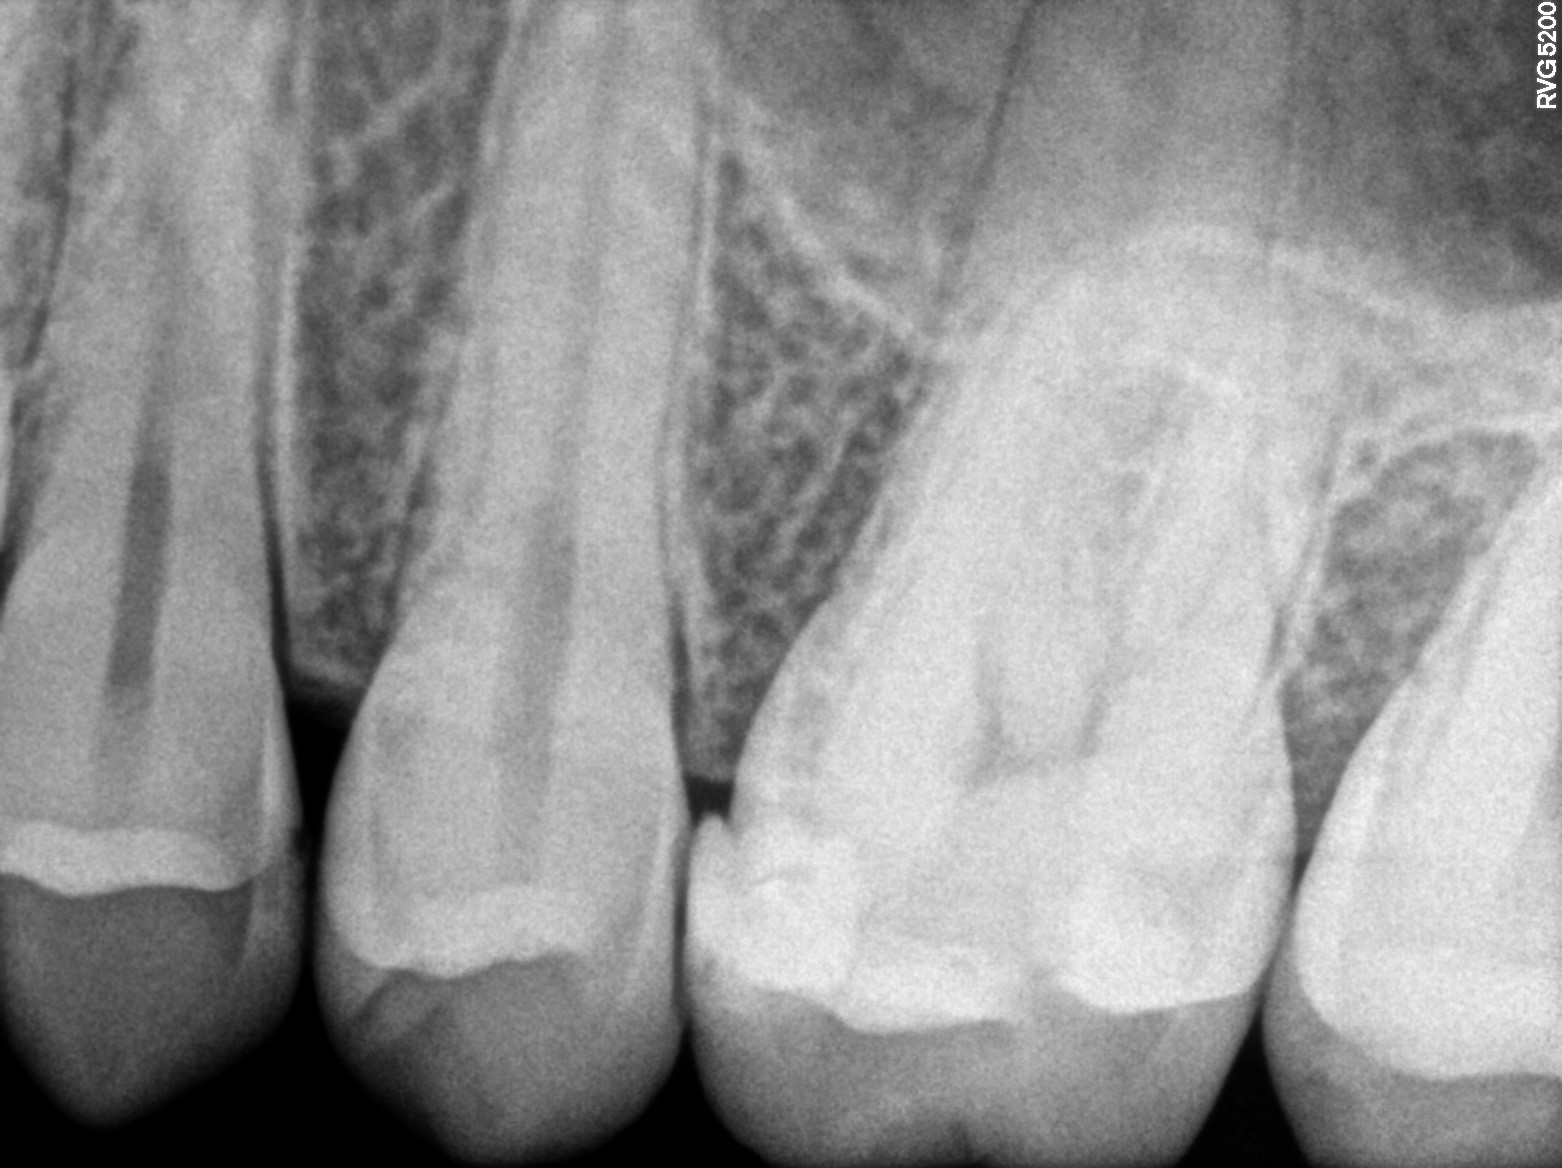

Dental Radiographs FHIR: DocumentReference · LOINC 24641-7

R5...5.jpg

24641-7